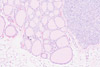

These are sample photos of microscope slide specimens.

Both enlarged images and thumbnails were captured with a DSLR camera using our

DSLR Microscope Adapter and resized for the website.

Cerebrum (40x) Thyroid (20x) Kidney (40x)